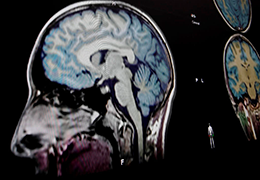

Segmentation

Segmentation of tissue (e.g., isolating the brain, differentiating gray and white matter) is performed using region-growing methods, filter operations as well as the application of 3D templates. Using the mouse it is very easy to explore a 3D volume with superimposed pseudocolor-coded statistical maps in a four-window representation showing a sagittal, coronal, transversal and oblique section. Based on a (segmented) 3D data set a three-dimensional reconstruction of the subjects' head and brain can be calculated and displayed from any specified viewpoint using volume or surface rendering.

Talairach transformation is performed in two steps. The first step consists of rotating the 3D data set for each subject to be aligned with the stereotaxic axes. For this step the location of the anterior commissure (AC) and the posterior commissure (PC) as well as two rotation parameters for midsagittal alignment has to be specified interactively. In the second step the extreme points of the cerebrum are specified. These points together with the AC and PC coordinates are then used to scale the 3D data sets into the dimensions of the standard brain of the Talairach and Tournaux atlas.

The surface reconstruction procedure starts with a sphere (recursively tesselated icosahedron) or a rectangle, which slowly wraps around a (segmented) volume data set. In order to avoid topological defects and to let the surface smoothly grow into deep sulci, a dynamic mesh algorithm was developed which automatically invents new polygons on the fly at places where they are needed. A reconstructed cortical surface may be inflated, cut interactively and slowly unfolded minimizing areal distortions. Statistical 3D maps may be superimposed on reconstructed, inflated or flattened cortex. Signal time courses may be invoked by simply pointing to any region of a visualized surface.